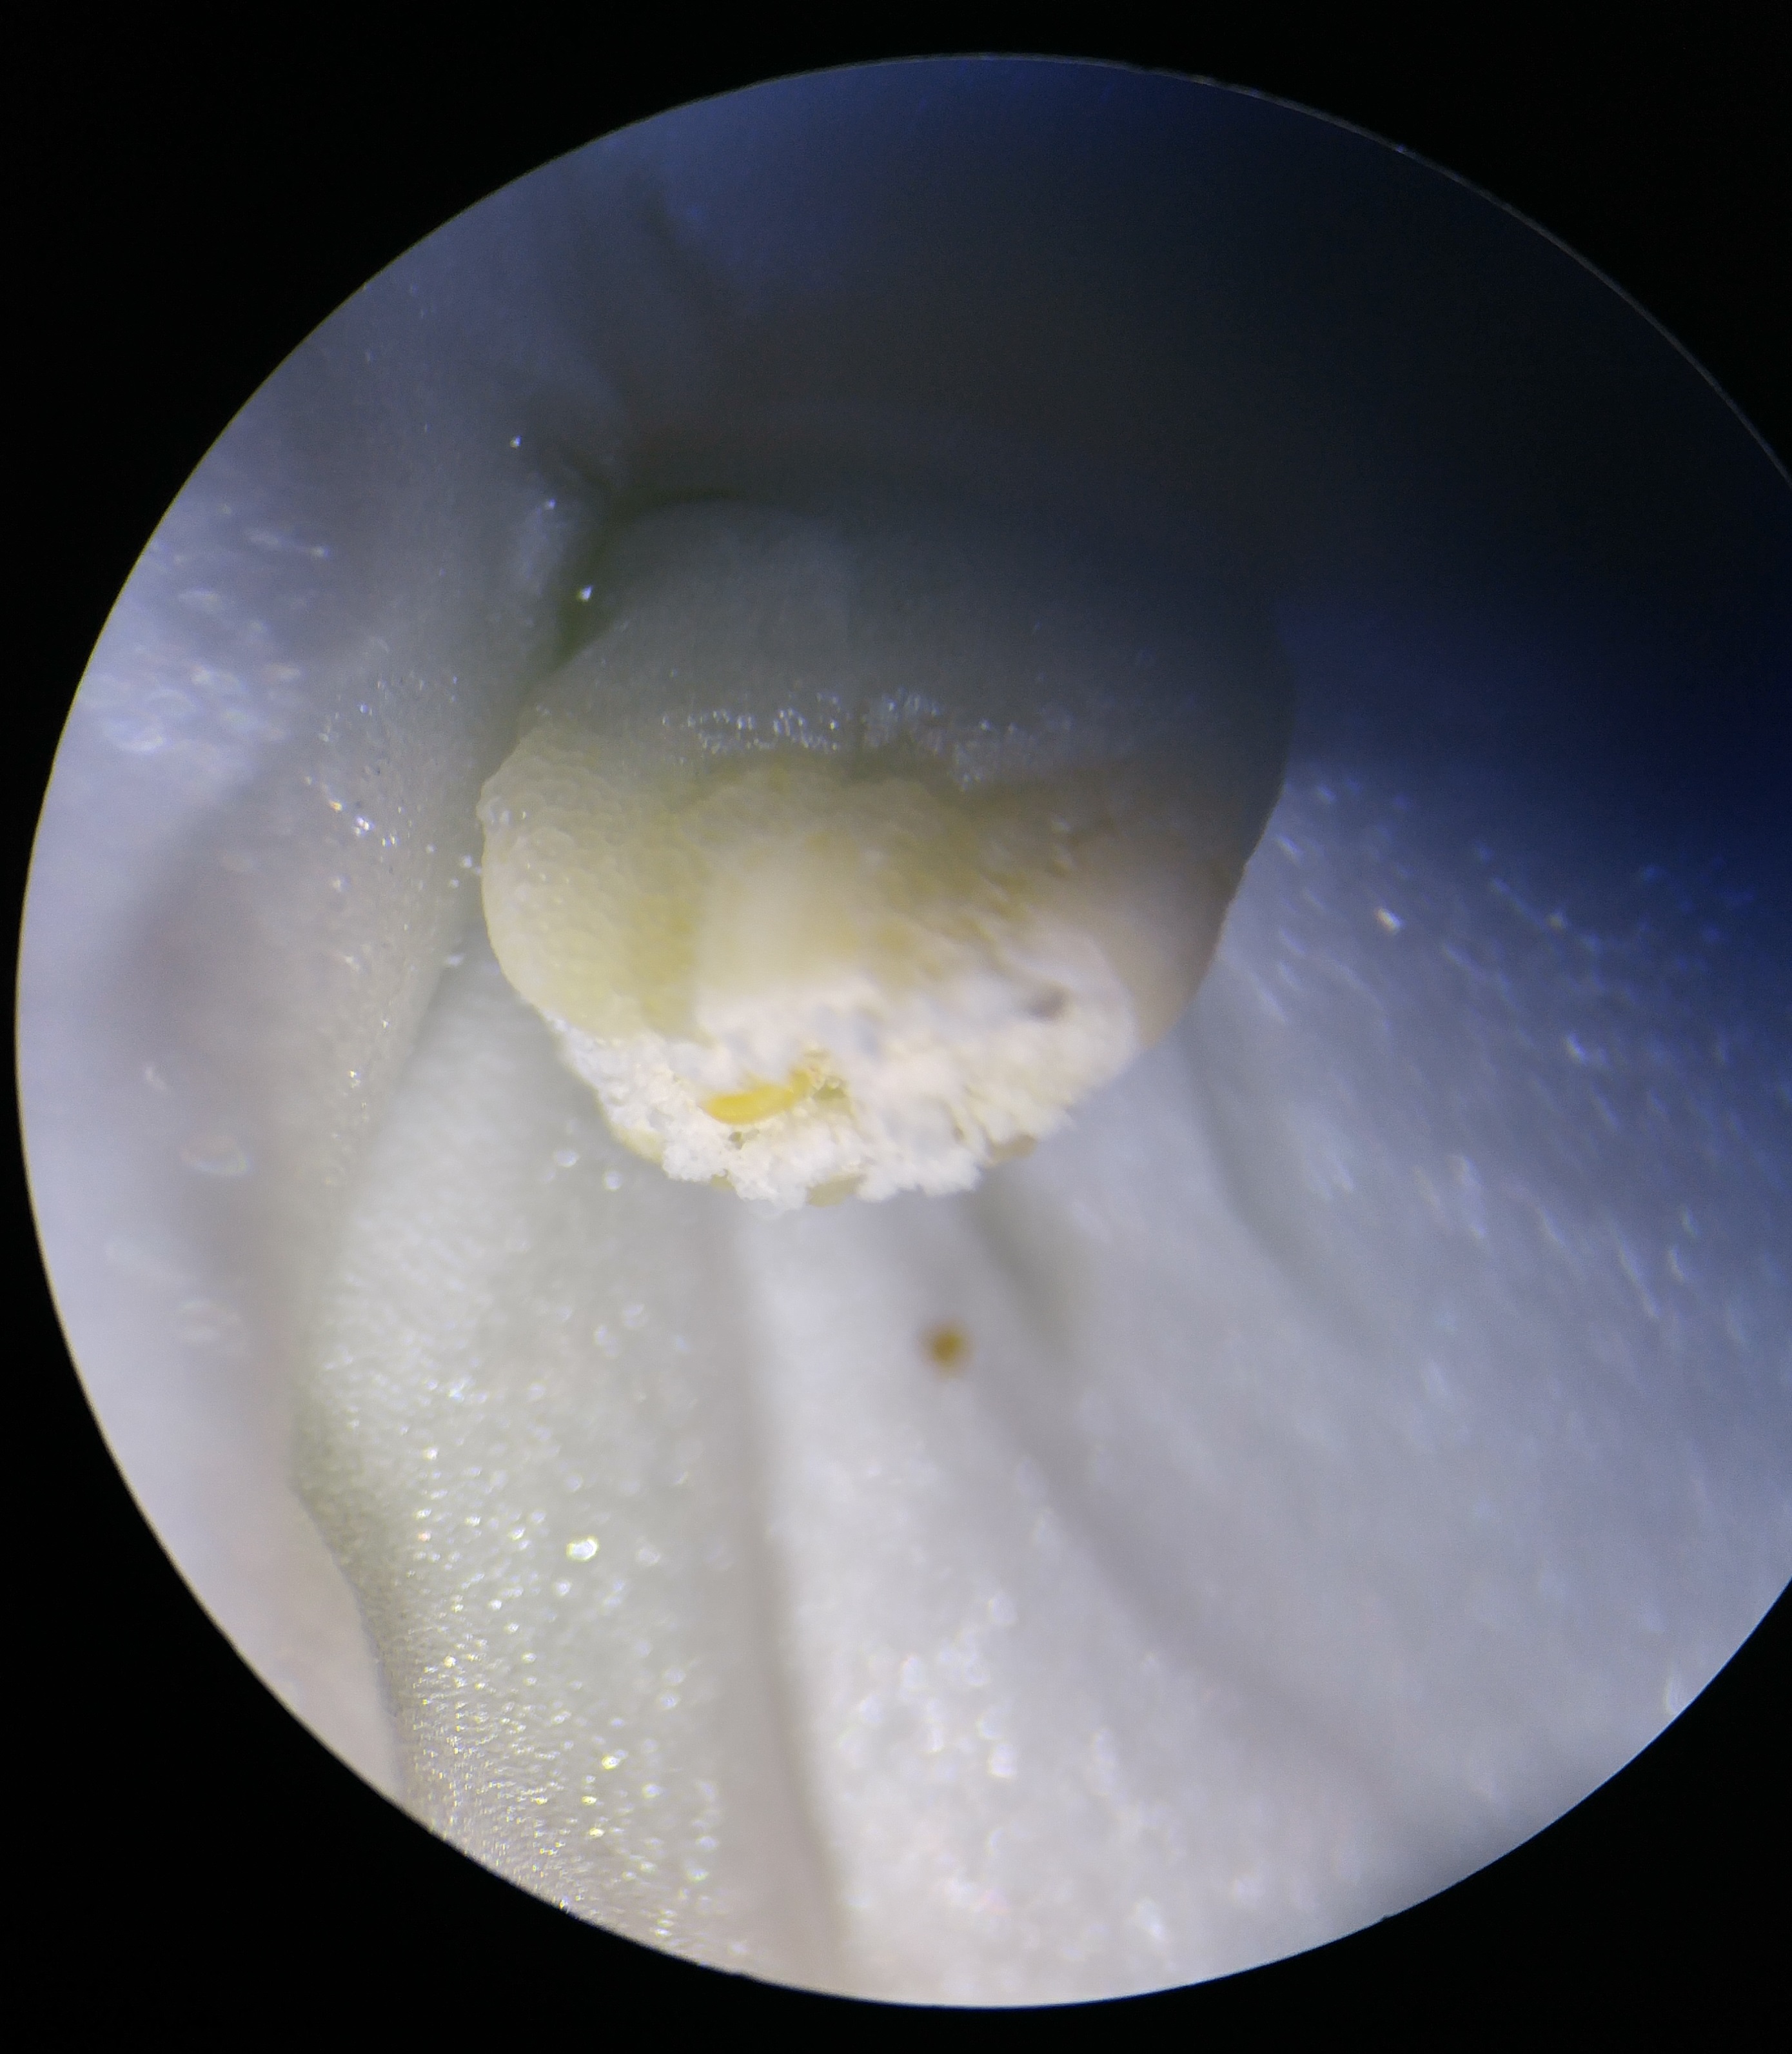

All Rights Reserved. Noah Zalev, 2017